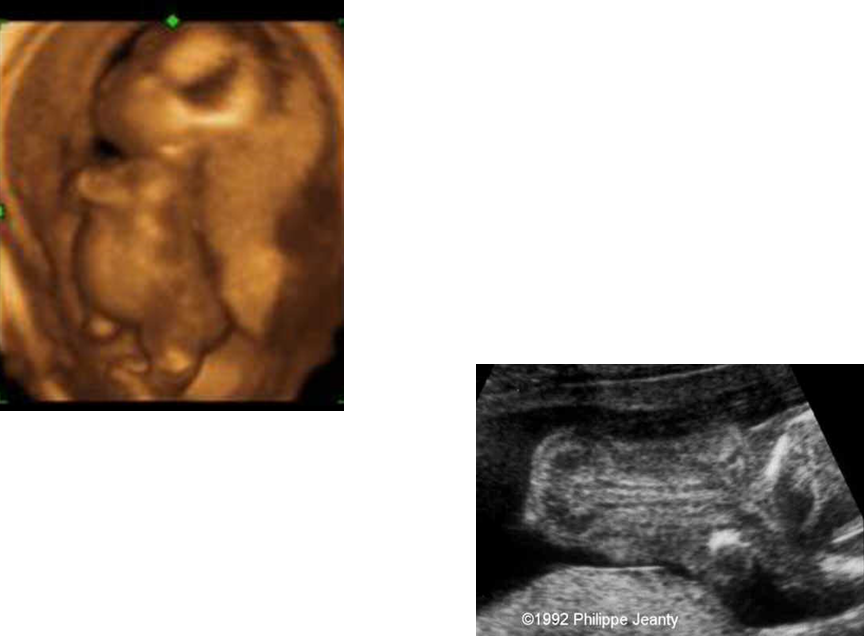

What are these images showing?

Achondrogenesis